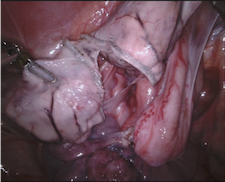

Our challenge was made up of 3 sub-problems. The first was binary instrument segmentation, where each frame was separated into da Vinci Xi instruments and a background class, which contained an ultrasound probe, surgical clips and porcine tissues. The second task was instrument part segmentation, where we scored the participants on whether they could correctly segment each articulating part of the instrument (see Fig. 3). Our final task was to segment and classify the instruments (see Fig. 4).

We provided the first 225 frames of 8 sequences as training data and kept the last 75 frames of those 8 sequences as test data. 2 of the full 300 frame sequences were kept as test sequences. Test labels were kept hidden from the participants. Our datasets contain 7 different robotic surgical instruments. The Large Needle Driver, Prograsp Forceps, Monopolar Curved Scissors, Cadiere Forceps, Bipolar Forceps, Vessel Sealer and additionally a drop-in ultrasound probe, which is typically held in the jaws of the Prograsp Forceps instrument. Samples from the training datasets are depicted in Fig. 2 and examples of the different instrument types are shown in Figure 3 and 4.

IV-C Parts Segmentation

Our second challenge was on instrument part segmentation where the participants were challenged to divide the binary instrument labels into a shaft, wrist and jaws. As in the binary segmentation challenge, the drop-in US probe and other man-made devices as well as all anatomical objects were to be labelled as background. We compute the mean IoU for each frame of each dataset and for frames where no instance of a class occurred, such as when the shaft is withdrawn completely from the field of view. Nine teams participated in this challenge, the only team abstaining was from IIT Delhi.

IV-D Type Segmentation

The final challenge was to identify each instrument type from the list of Large Needle Driver, Prograsp Forceps, Monopolar Curved Scissors, Vessel Sealer, Fenestrated Bipolar Forceps and Grasping Retractor (see Fig. 4). Only 6 teams participated in this challenge, due particularly to the significant increase in difficulty in recognizing many of the da Vinci instruments from one another.